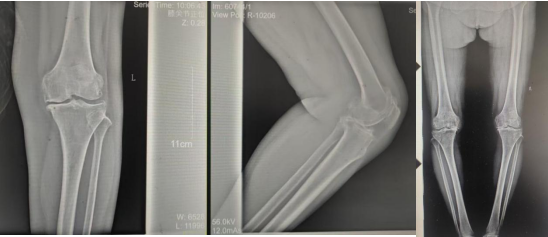

術(shù)前影像資料

張女士于10年前勞累后左膝疼痛,干活后疼痛較重,陰雨天及受涼時(shí)疼痛明顯,行走時(shí)可聞及關(guān)節(jié)內(nèi)異響,時(shí)有“打軟腿”現(xiàn)象,曾到附近多家醫(yī)院診治,給予膝關(guān)節(jié)針灸、膏藥外貼、口服藥物等“保守”治療,治療后疼痛癥狀略有好轉(zhuǎn),但易復(fù)發(fā);近2年患者左膝關(guān)節(jié)疼痛逐漸加重,行走跛行,下蹲及上下樓梯困難,活動時(shí)疼痛明顯,休息、保守治療后疼痛無明顯好轉(zhuǎn)。

張女士的鄰居看她上下樓如此困難,日常生活都很受影響,因其以前在我院看過腰椎,效果良好,故介紹張女士來我院找萬昌勝主治醫(yī)師進(jìn)行咨詢問診。萬醫(yī)生了解情況后帶她到我院關(guān)節(jié)外科進(jìn)行更專業(yè)的診治。關(guān)節(jié)外科門診醫(yī)師結(jié)合癥狀體征及影像學(xué)檢查,建議入院手術(shù)治療,以“左膝骨性關(guān)節(jié)炎伴膝內(nèi)翻、高血壓病”收住入院。